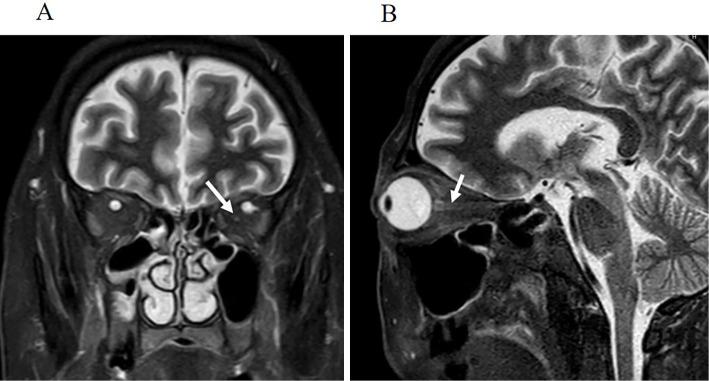

Pembrolizumab is a monoclonal antibody with anti-tumor effects. Only a few reports have previously described retrobulbar optic neuritis induced by pembrolizumab. We herein report the case of a 63-year-old man with advanced lung adenocarcinoma who received cisplatin, pemetrexed, and pembrolizumab combination therapy for six months. Following treatment, a visual field test showed a left central scotoma. Imaging studies showed left optic neuritis without brain metastasis. Blood tests showed an elevated serum creatinine level. He was diagnosed with retrobulbar optic neuritis and pembrolizumab-induced renal failure. After receiving corticosteroid treatment, his renal function rapidly improved. The optic neuritis improved somewhat, but it was not adequately resolved.

派姆单抗是一种具有抗肿瘤作用的单克隆抗体。以前只有少数报告描述过派姆单抗引起的球后视神经炎。本文报告了 1 例 63 岁男性,患有晚期肺腺癌,接受顺铂、培美曲塞和派姆单抗联合治疗 6 个月。治疗后,视野检查显示左眼中央性暗点。影像学检查显示左侧视神经炎,无脑转移。血液检查显示血清肌酐水平升高。他被诊断为球后视神经炎和派姆单抗引起的肾衰竭。接受皮质类固醇治疗后,他的肾功能迅速改善。视神经炎有所改善,但并未完全缓解。